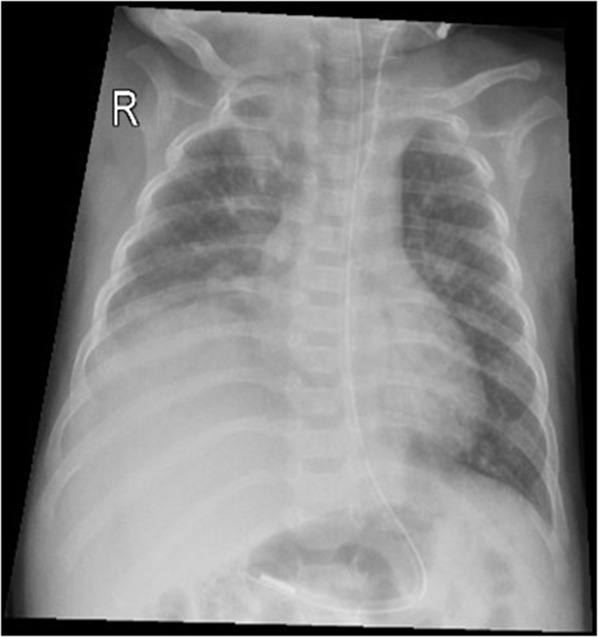

膈肌麻痹(DP)可由中枢神经系统病理或周围神经损伤引起。肋间胸引流术治疗气胸后直接损伤膈神经是一种少见的并发症。我们报告了一名4个月大的婴儿,早产27周,于2023年入住阿曼马斯喀特一家三级医院儿科重症监护室,患有严重呼吸道合胞病毒细支气管炎,需要插管和机械通气(MV)。他的病情因右侧气胸而复杂化,需要植入ICD。拔管后,患者持续呼吸急促,无法脱离无创通气。胸部x线及透视显示右侧膈球高且运动矛盾。他在右膈肌伸展术后明显好转,并于伸展术后第9天出院回家。

Diaphragmatic paralysis (DP) can occur due to central nervous system pathology or peripheral nerve injury. Direct injury to the phrenic nerve after intercostal chest drain (ICD) insertion for treatment of pneumothorax is an infrequent complication. We present a 4-month-old infant, ex-preterm 27 weeks, who was admitted to a tertiary care hospital paediatric intensive care unit in Muscat, Oman, in 2023 with severe respiratory syncytial virus bronchiolitis and required intubation and mechanical ventilation (MV). His illness was complicated by right-side pneumothorax that required ICD insertion. Post-extubation, he had persistent tachypnoea with the inability to be weaned from non-invasive ventilation. Chest X-ray (CXR) and fluoroscopy showed a high right diaphragm dome with paradoxical movements. He improved dramatically after the plication of the right diaphragm and was discharged home on the 9th day after the plication.